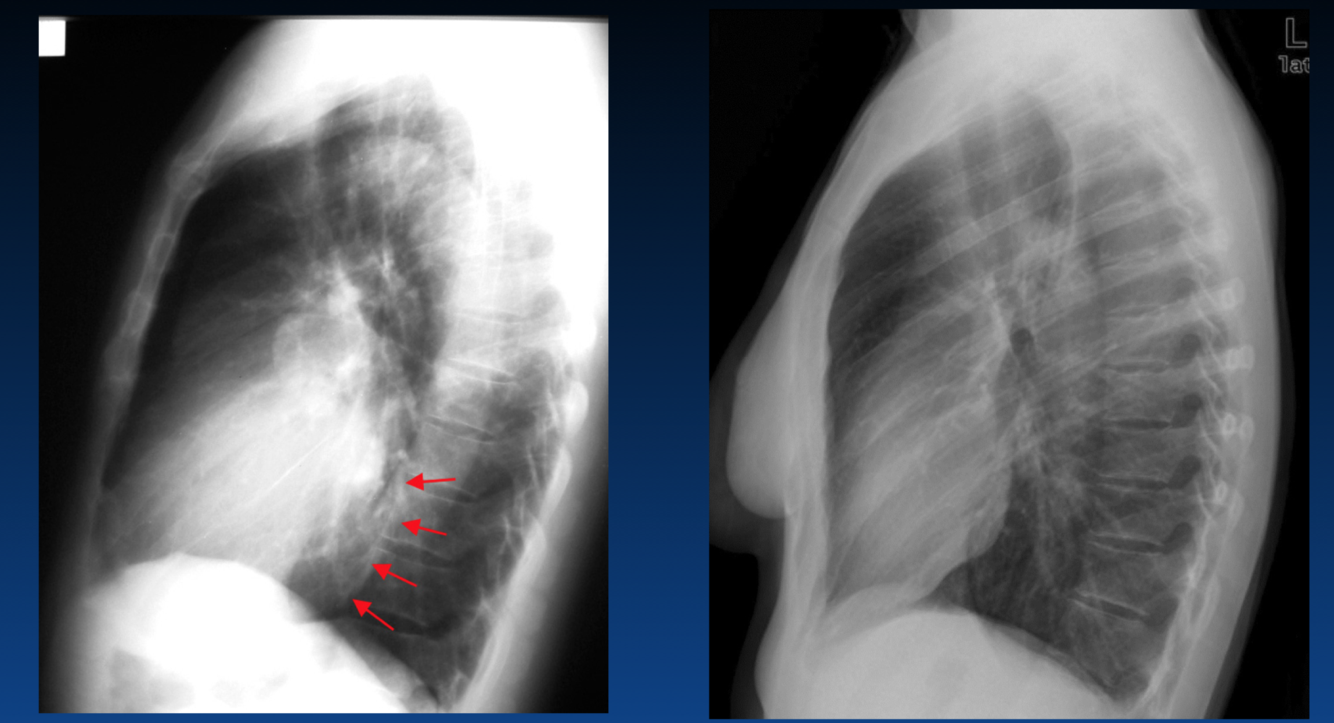

The left atrium is enlarged. What sign is the arrow pointing that indicates this?